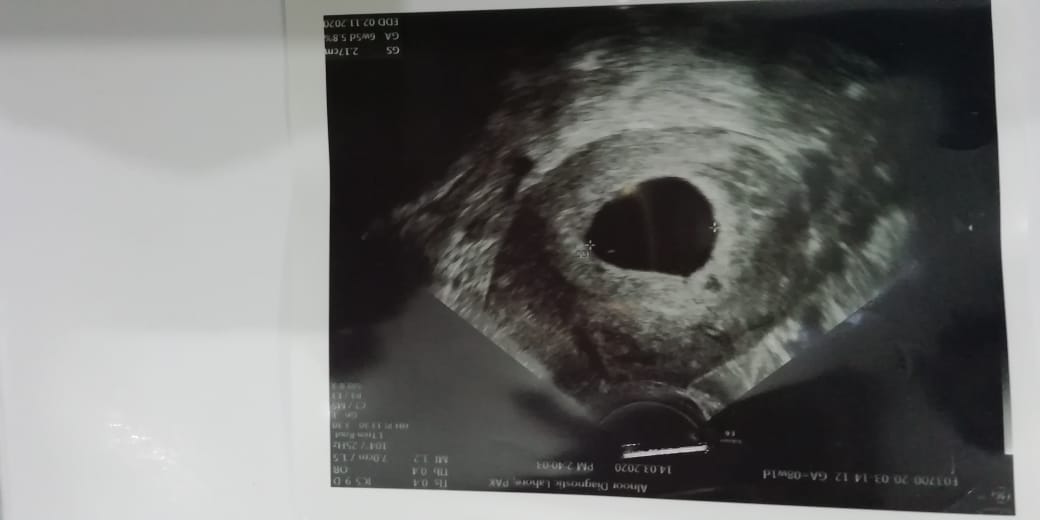

I'm mother of 1.9 months old daughter via csection. I had my last periods on 17th of jan 2020.. And got positive hcg on 19th of Feb. My doc advised for Pelvic scan for fca on 15th March to let know about fetal heartbeat. I felt very much little blood spot along with white discharge 2 weeks ago. Attaching pics of files.I didn't have heatbeat of baby yet. My doc have asked to do scan again after 2 weeks. I want to know wheter there are any chances of healthy pregnancy now after this situation? also I feel pain right below abdomen. Attaching pic for refrence. Kindly help meI am so much worried

according 2 LMP ur pregnancy is 8weeks plus. idealy fetal cardiac activity cms on 6 weeks and ur u/s report is also indicating missed miscarige. lets wait and rescan after 2 weeks.

This is Missed Abortion as no fetal pole seen but wait and rescan after 2 weeks.